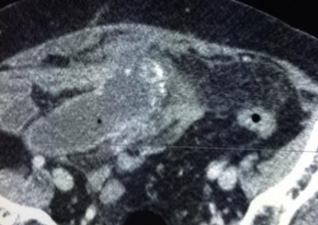

CT scan κοιλίας. Παρουσία ασβεστώσεων, κυστικο-συμπαγών περιοχών και λιπώδους ιστού, ενδεικτικά τερατώματος δεξιάς πλευράς (Ευγενική παραχώρηση Dr. V. Penopoulos)